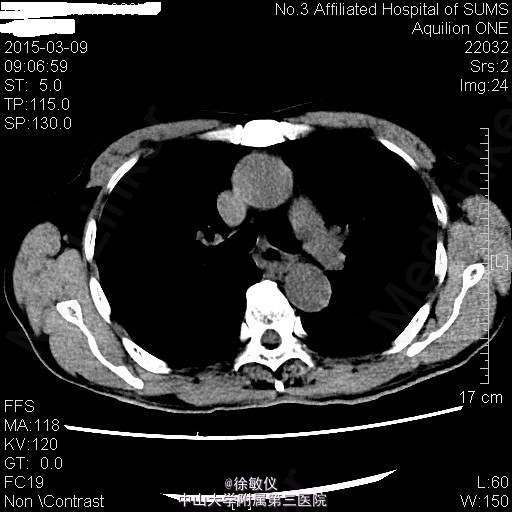

老年男性,主诉:进行性吞咽困难1月 现病史:患者1月前无明显诱因出现吞咽梗阻感,以进食粗糙、过热食物时明显,进食半流质症状不明显,10天前就诊外院行胃镜检查提示:食管癌,活检病理"鳞状细胞癌"。

查体:无特殊。 胸部CT平扫+增强:中段食管癌,部分层面与胸主动脉分界欠清;纵隔多发小淋巴结。